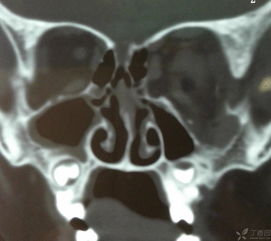

⑥腦脊液鼻漏:分泌物為透明清澈水樣,常見于先天性篩板、蝶竇骨缺損和顱前窩、顱中窩窩底骨折或手術(shù)外傷。